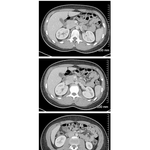

• Abdominal Scans: Axial CT Images (continued)

327. Abdominal Scans: Axial CT Images (continued)